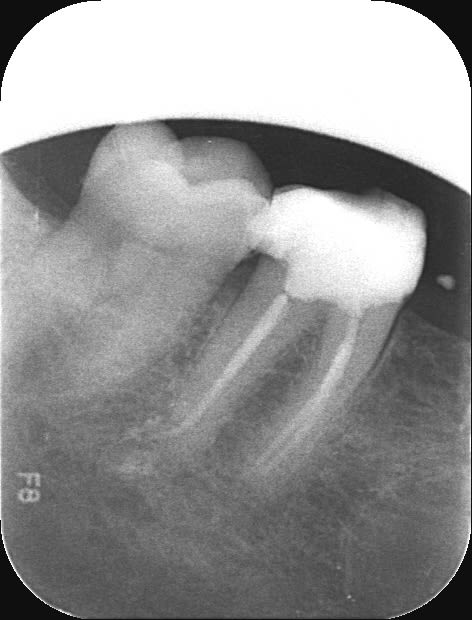

J'ai fait ma première molaire cet après-midi au Reciproc, j'ai fait qques premos + dents extraites + blocs résines la semaine dernière.

Bon les mêmes impressions que sur bloc : vibrations, sensations étranges de ne pas faire grand-chose et ... l'instrument qui avance quand même, pas aussi vite et pas de façon aussi angoissante que le Hero (sensation d'aspiration), mais bon une sorte de tressautement sans avoir besoin d'appuyer beuacoup.

Beaucoup de débris (due à la forme de l'instrument, angle de coupe etc..) et tassement entre les spires importants : necessité de travailler sous EDTA et Hypo tout le temps + nettoyer l'instrument assez souvent.

Trois canaux en 10 minutes .. alors on fait trainer en pompant au cone de gutta, en calibrant les cones, ..etc..

J'ai mis la radio pas pour la beauté de l'endo (ni celle de la radio :p) )mais parce que les deux mésiaux étaient pas mal fin +/- calicifiés, que j'ai du faire une butée au flare an voulant les élargir, conclusion impossible de passer un 8, j'y suis allé à l'instrument direct qui gentiment est descendu tout seul ..